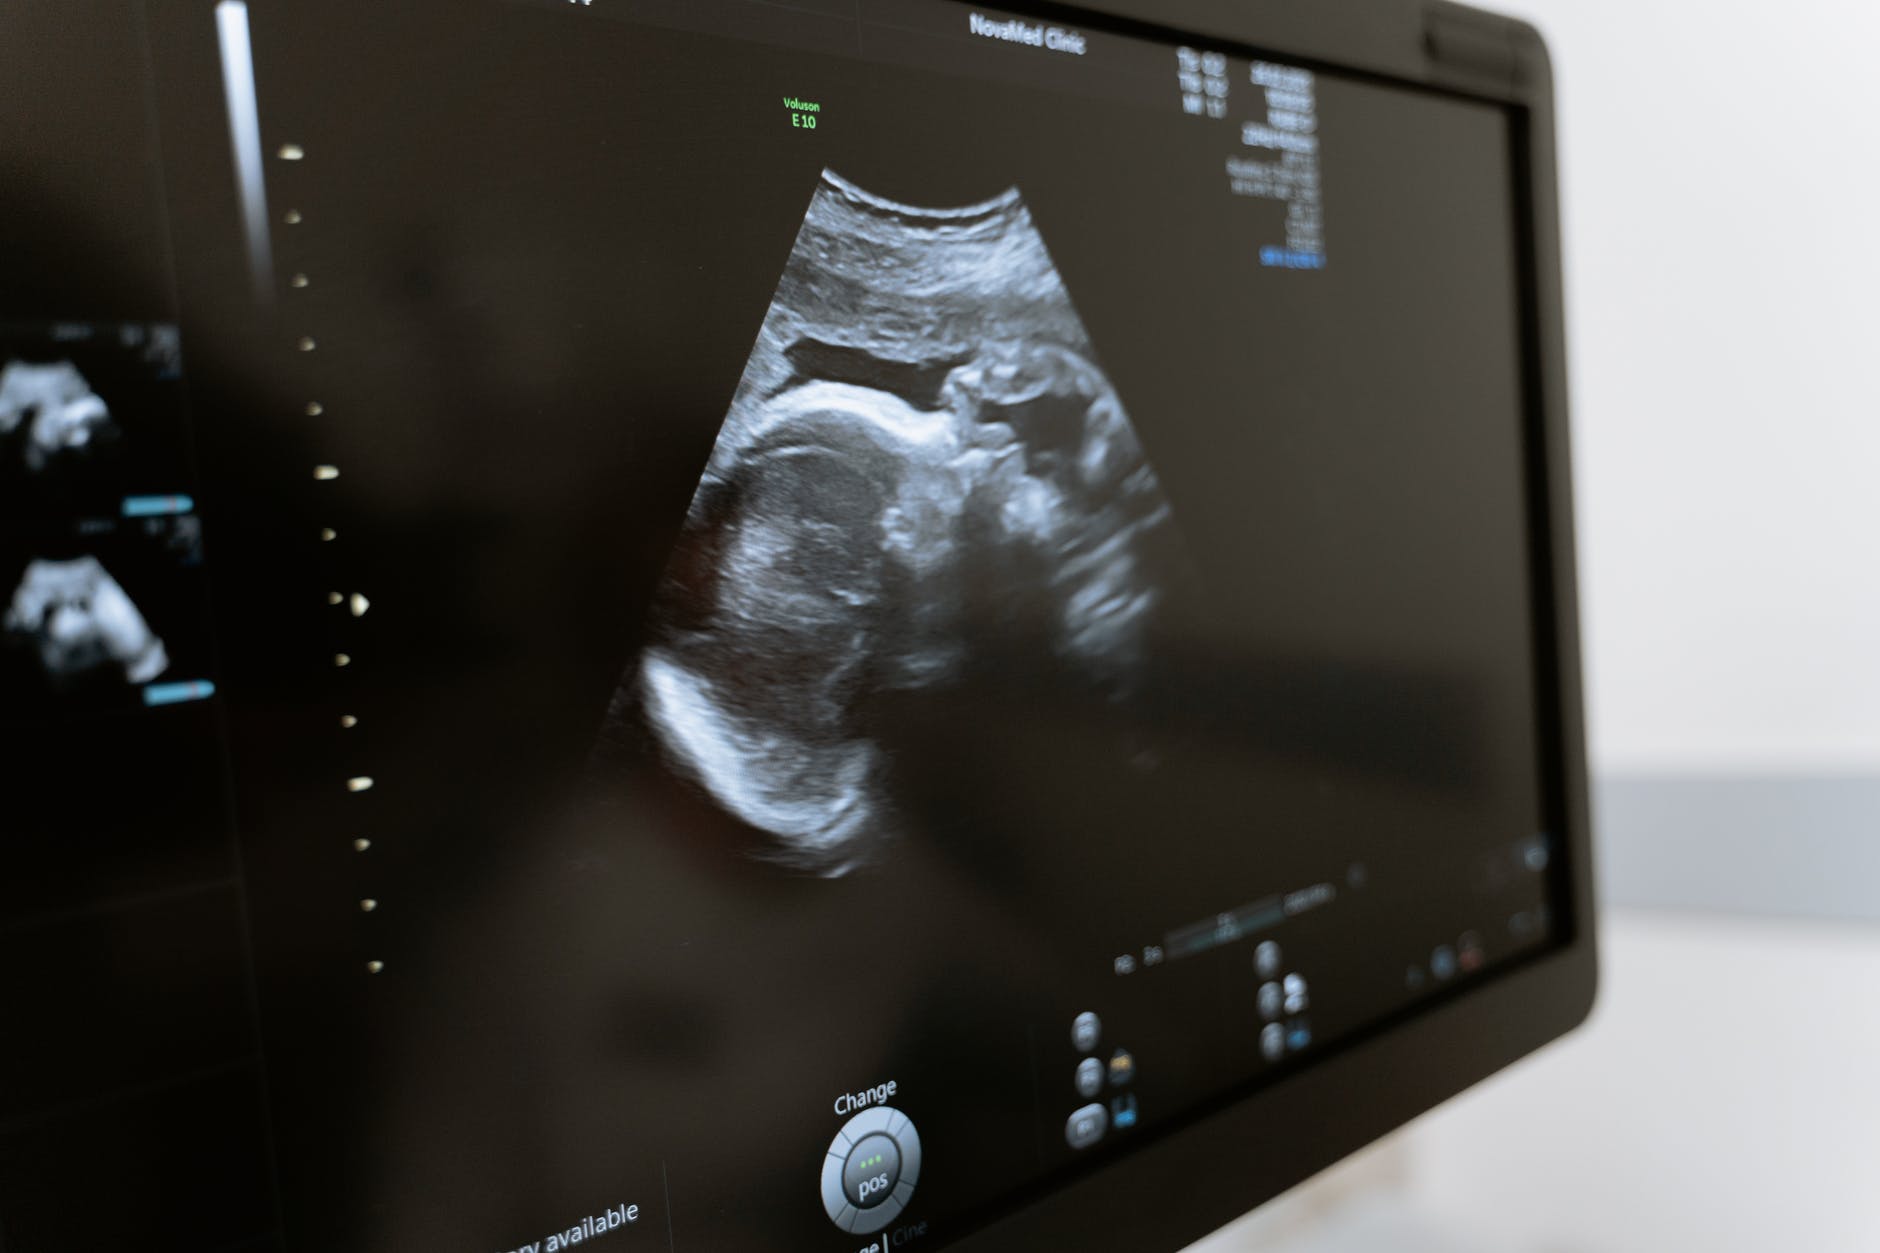

L’ecografia transvaginale è una tecnica diagnostica che permette di studiare la morfologia e lo stato di salute degli organi genitali interni femminili, ossia il collo dell’utero, l’utero, le salpingi o le ovaie. Una sonda rivestita da una pellicola ricoperta di gel viene introdotta nella vagina, e qui emette ultrasuoni (onde sonore a elevata frequenza, non udibili dall’orecchio umano) che sono riflessi in modo differente dai tipi di tessuti circostanti.I segnali provenienti dai tessuti sono registrati da un computer che ricostruisce su un monitor le immagini degli organi pelvici. L’esame serve a ipotizzare l’origine di sanguinamenti o di dolori pelvici (infiammazioni possibili cause di infertilità). Inoltre è utile a studiare la natura delle cisti ovariche, il rivestimento interno dell’utero (endometrio) e gli ingrossamenti della parete dell’utero, e inoltre a individuare l’eventuale presenza di tumori.

Questo tipo di ecografia viene normalmente richiesta per sanguinamenti anomali, dolori pelvici di origine ignota, amenorrea, per donne con problemi di infertilità, malformazioni congenite di utero e ovaie, e quando il medico ha un sospetto di tumori o infezioni. Può essere inoltre impiegata al termine del primo mese di gravidanza perché permette di evidenziare più precocemente le immagini dell’embrione.